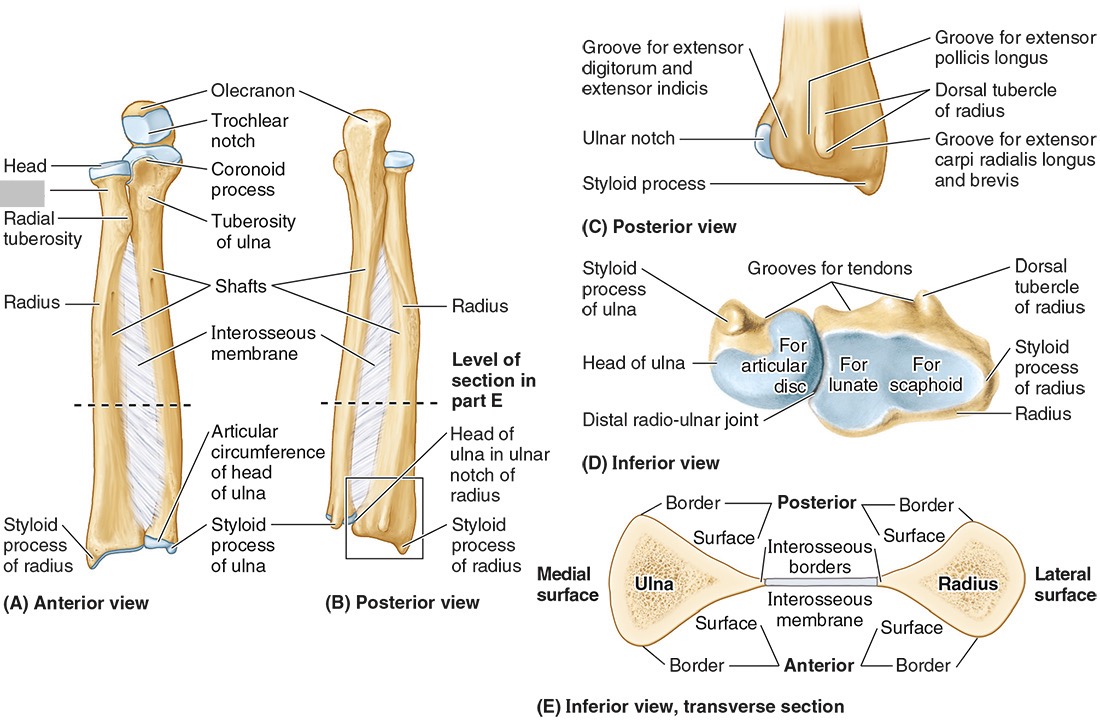

The ______ connects to the carpal bones of the hand at the wrist joint. The _____ widens distally to provide the proximal articular surface of the wrist (remember, the _____ is on thumb side of the wrist!)

(all the blanks are the same word)

Radius

The head of the radius

The neck of the radius

The radial tuberosity

The ulnar notch

The styloid process

The ____ is the medial forearm bone

Ulna

the olecranon (superior)

The coronoid processes (inferior)

The trochlear notch

The tuberosity of the ulna

The radial notch

The head of the ulna

Distal radio-ulnar joint